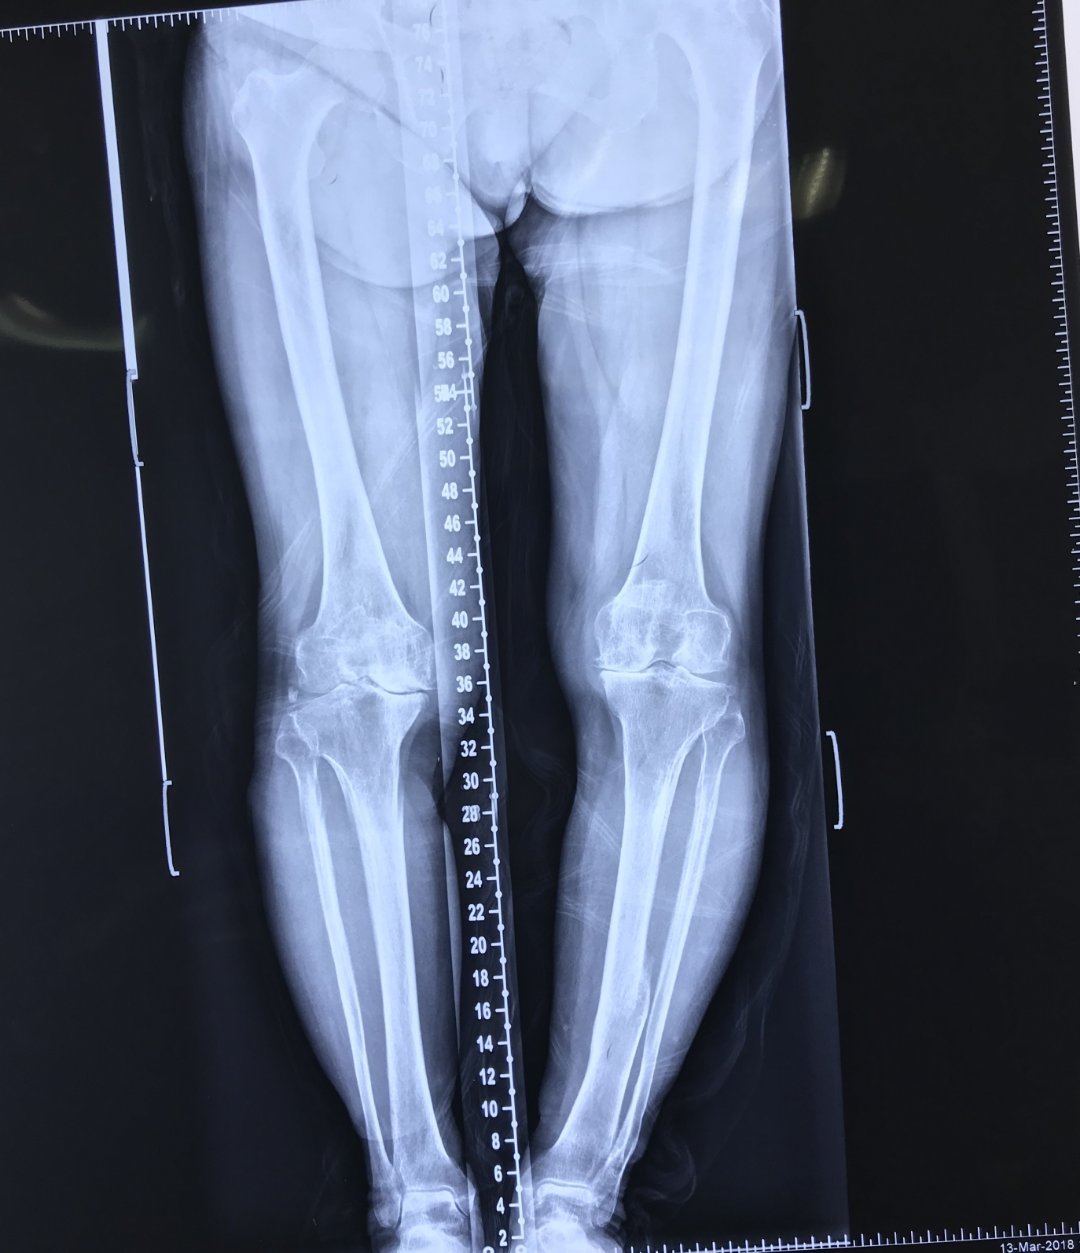

正常人的膝盖骨图片,正常人的膝盖x片图片

正常人的膝盖x片图片

正常膝关节x片

正常膝关节x光片图